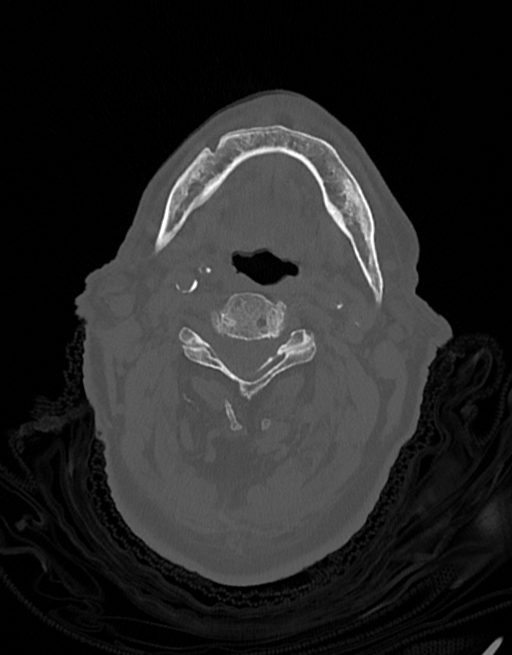

در سي تي اسکن اسپيرال نازو فارنکس با و بدون کنتراست (مولتي ديدکتور 16 با مقاطع ظريف و بازسازي هاي ساژيتال و کرونال):

– توده نسج نرمي به ابعاد mm 40 x 45 x 60 در ناحيه پاروتيد راست، با enhancement هتروژن پس از تزريق کنتراست مشهود است که مطرح کننده آدنوم پاروتيد مي باشد.

– شواهدي از تهاجم توده به استخوان و عروق اطراف مشهود نيست .

– کلسيفيکاسيون در ديواره شريان هاي کاروتيد دو طرف مشهود است .

– بررسي بافتي توده پاروتيد راست پيشنهاد مي شود .